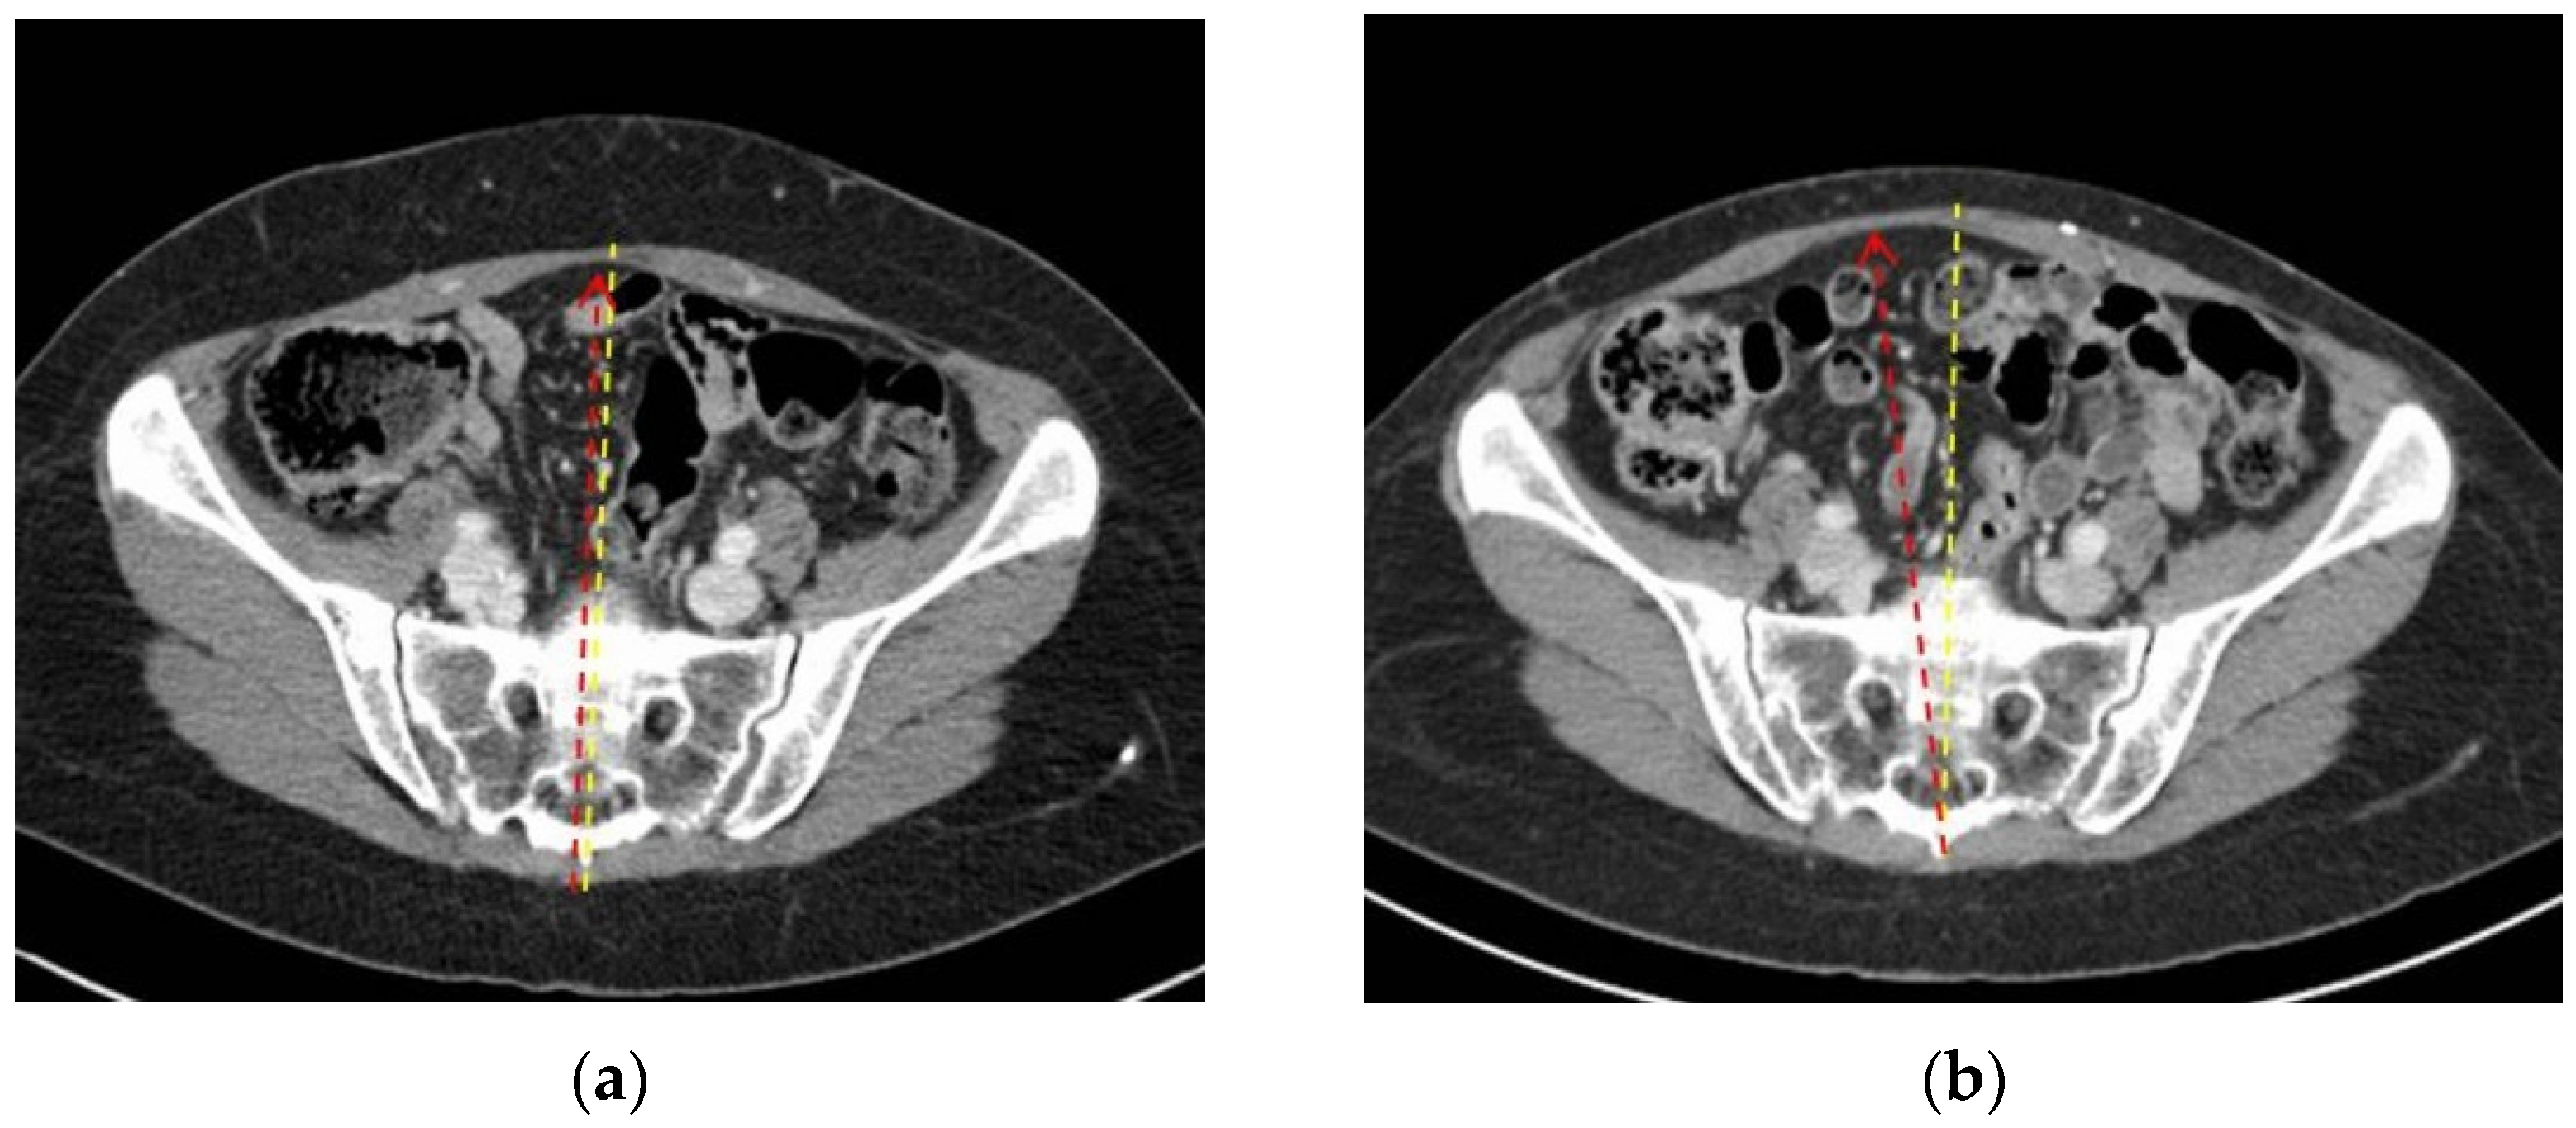

3.1. Two-Dimensional Evaluation